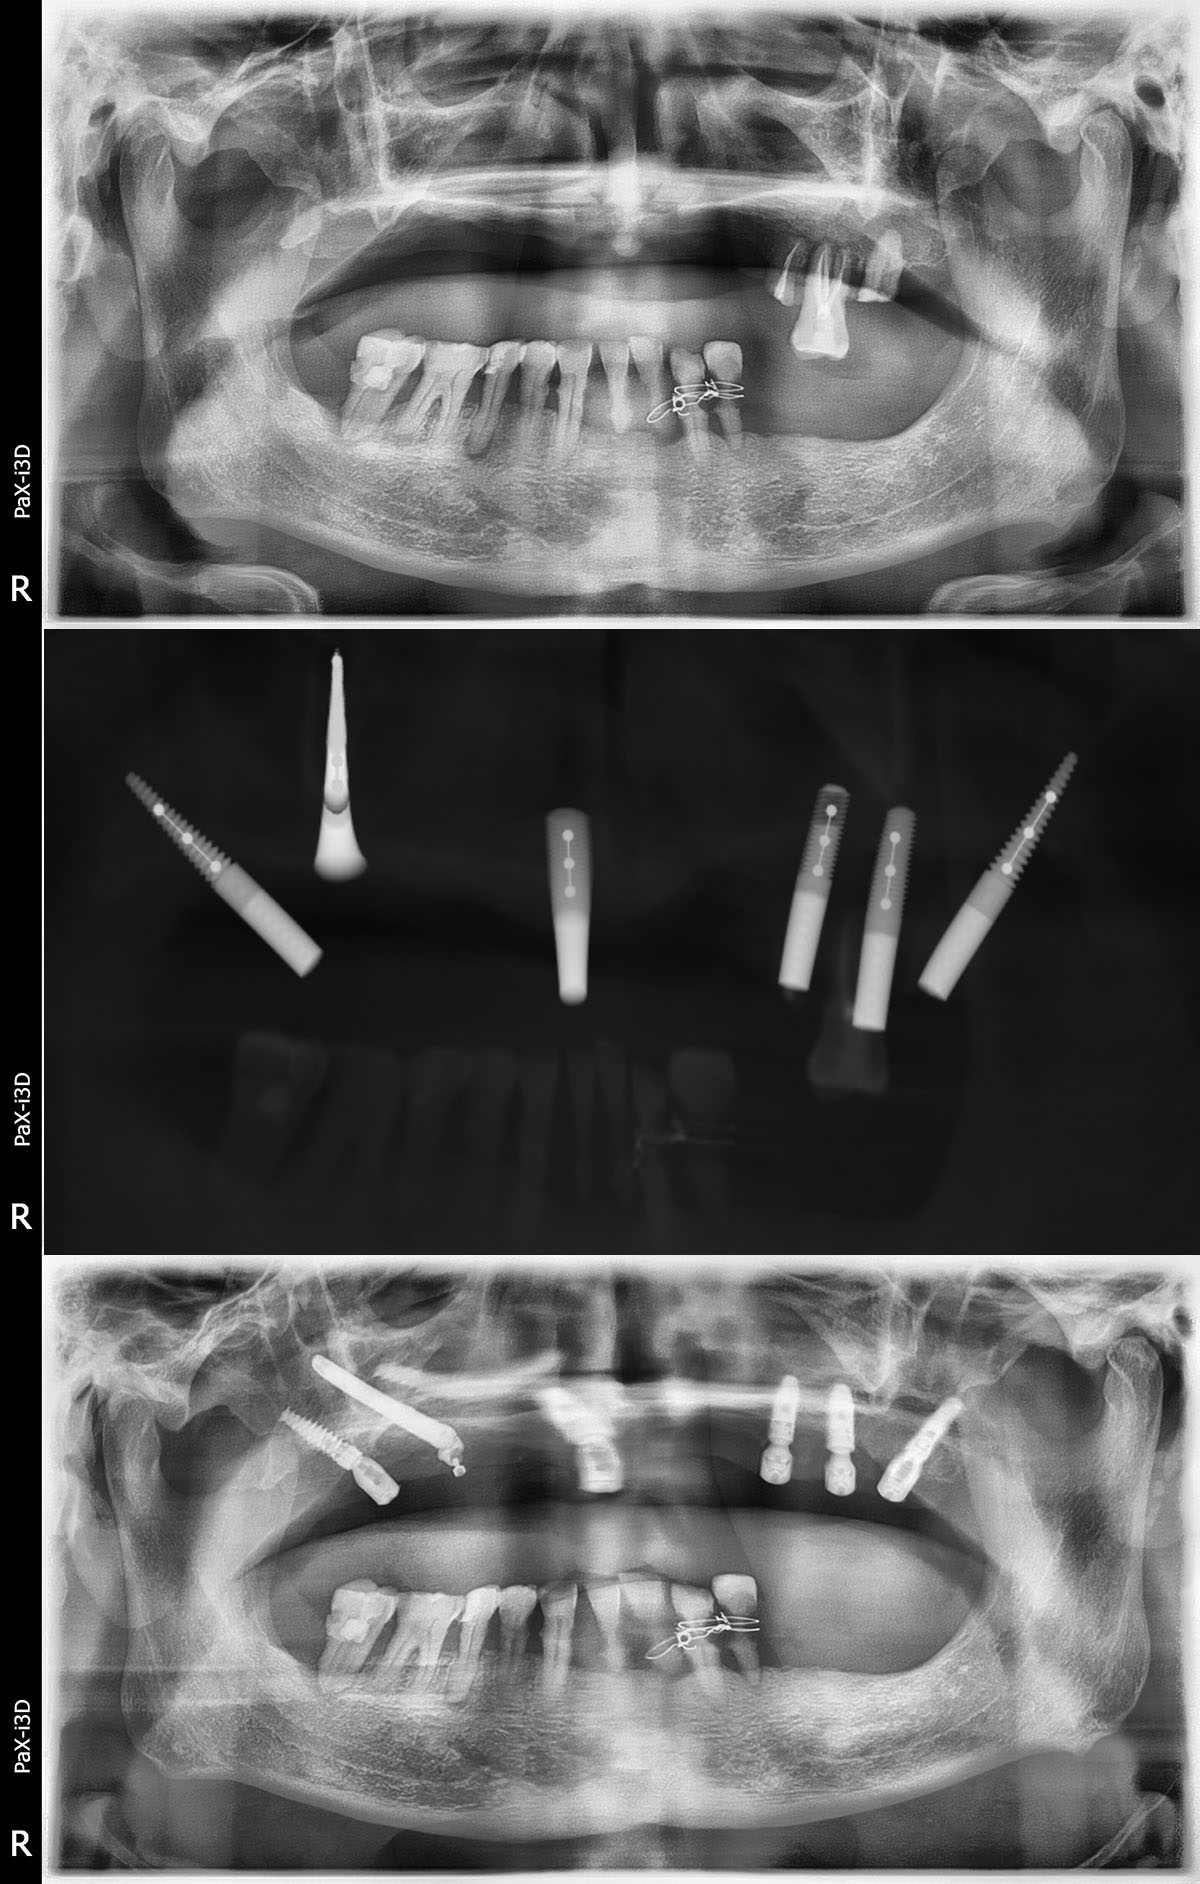

如今,种植牙越来越为人所知,但如果上下颌骨条件不佳,种植牙将非常困难,不仅要大量植骨,而且等待的时间也延长。9月26日,贝臣齿科通过高难度“穿颧种植术”,在一天内为一名患者成功种上了半口牙。

种植牙是缺失牙的常规修复手段,刘先生咨询了多家医院,很多医生对他的口腔状况都束手无策。并得出了一致的结论:上颌牙槽骨极度萎缩,按传统的种植方法,不仅操作难度极大,而且术后恢复比较缓慢,种植体也很容易失败。这让刘先生十分无奈。在四处打听的过程中得知,贝臣齿科国际牙种植中心团队正是国内为数不多掌握穿颧种植术的团队。经过详细的检查和问诊后,得知可以通过穿颧种植手术解决缺牙问题,让他很是欢喜。

“穿颧种植修复”是将种植体植入到人体较硬的骨头——颧骨,它可避免传统种植术取骨、植骨等手术风险,一天就可种好全口牙,其受力效果好、稳定性强,可使用一生。

穿颧种植术是一种可靠的修复方法。其主要优点是避免了大量植骨手术,缩短了治疗周期。颧种植体从后牙区牙槽嵴顶或偏腭侧植入,穿上颌窦进入颧骨,获得颧骨与上颌骨双重固位;同时在前牙区植入2至4枚常规种植体,可完成上颌无牙颌的固定修复。

通过术前检查的CT片以及检测结果,传统“一日得”种植术不适合刘先生,贝臣医生团队量身定制穿颧半口高难度治疗方案来帮助刘先生恢复一口好牙!穿颧种植方案就是贝臣医生团队经过分析后最终给出的治疗方案。事实上能做这一种植方案的医生“穿颧种植方案”少之又少。经过贝臣医生团队帮助刘先生实现重获新牙的愿望。

“穿颧种植体的长度是传统植体的3~4倍,因此起点的微小误差就可导致末端的严重偏离,所以术前应详细进行手术计划,CT检查对于了解双侧颧骨的情况必不可少。患者还应进行常规的全身及口腔颌面部的专科检查,排除相关禁忌症的存在。”